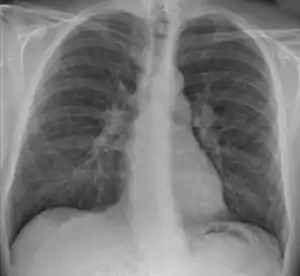

![]() | |

| Chest X-ray showing the typical nodularity of sarcoidosis, predominantly in the hila of the lungs. | |

Hilar adenopathy especially on the person's left (AP CXR)

Hilar adenopathy especially on the person's left (lateral CXR)

Hilar adenopathy especially on the person's left (coronal CT)

Hilar adenopathy especially on the person's left (transverse CT)